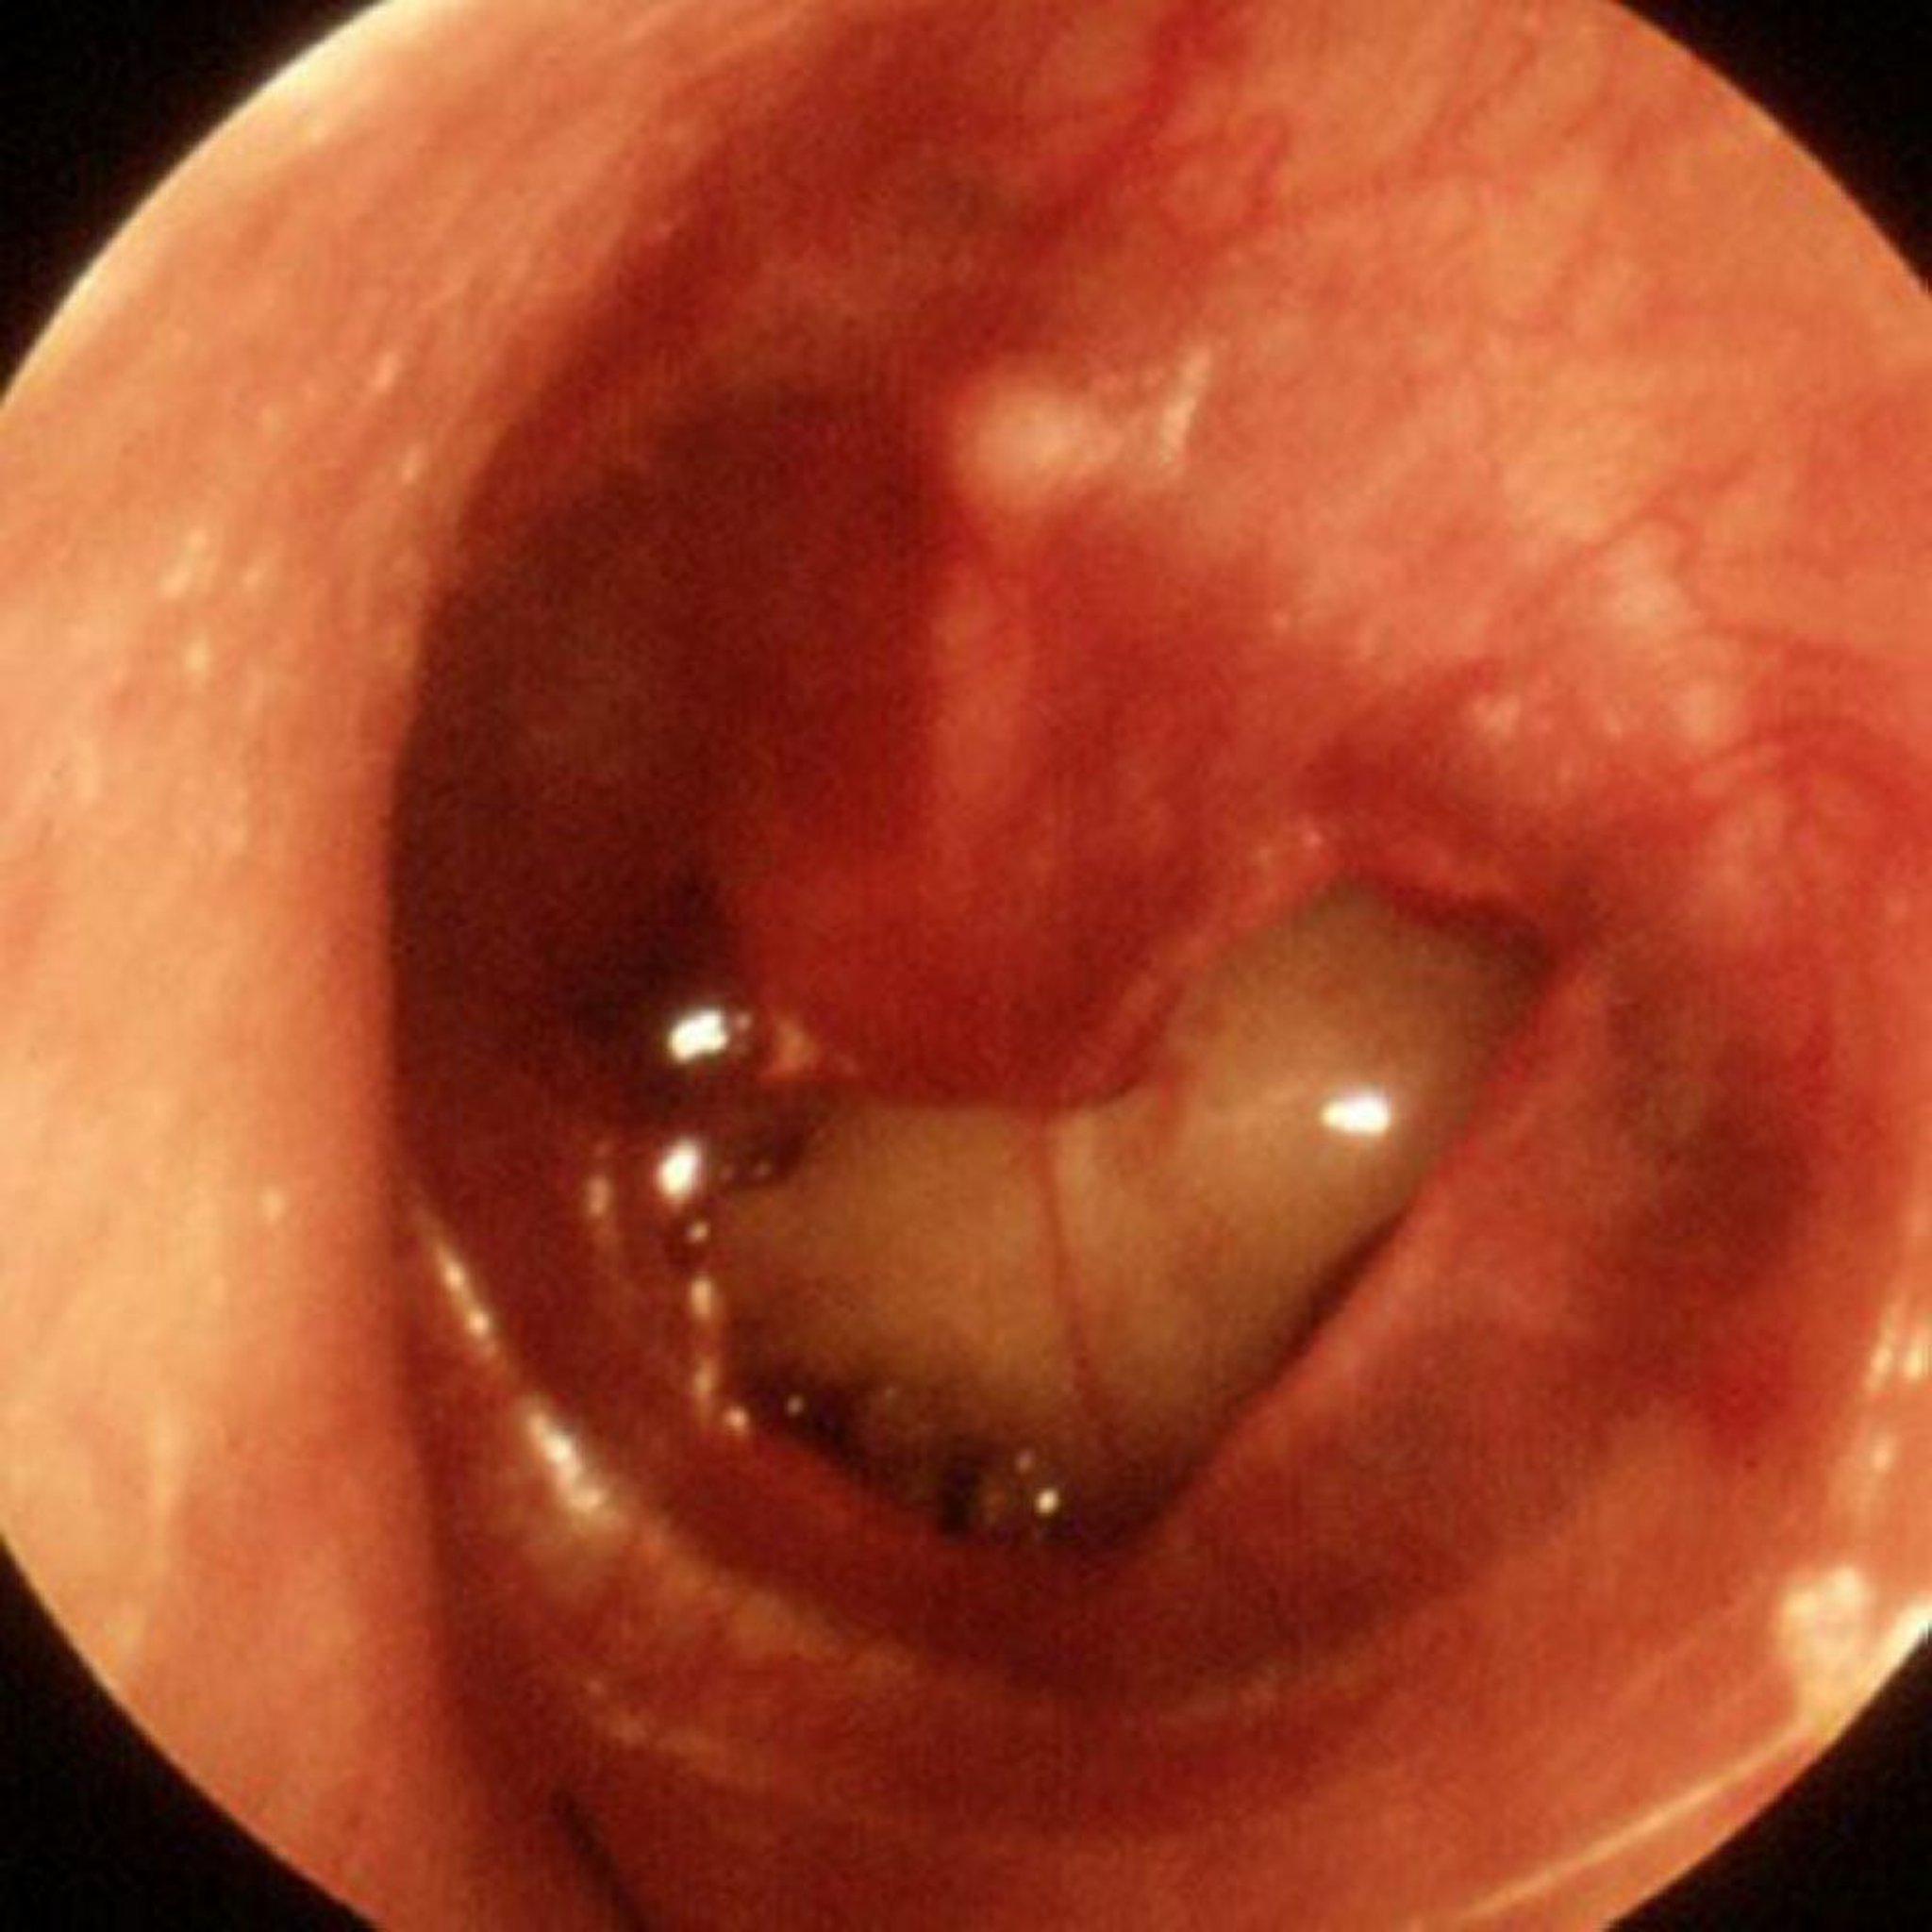

Травматическая перфорация барабанной перепонки

Большая травматическая перфорация видна на этом изображении.

Изображение предоставлено Piet van Hasselt, MD.